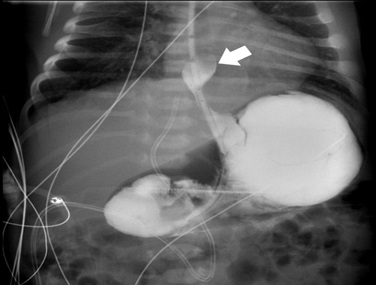

Upon admission to the pediatric intensive care unit, thoracoabdominal radiography (figure 3) and abdominal ultrasound demonstrated a partially intra-thoracic stomach, suggesting of a hiatal hernia with preserved diaphragm continuity. Echocardiogram revealed aortic isthmus narrowing with a maximum systolic gradient of 12 mmHg. The neonate was under continuous cardiorespiratory monitoring, and blood pressure, diuresis, and temperature were evaluated every four hours. He was breathing spontaneously with no signs of respiratory distress and had a nasogastric tube in passive drainage.

Figure 3: Thoracic and abdominal radiography on day 1 showing herniated intrathoracic stomach (arrow).